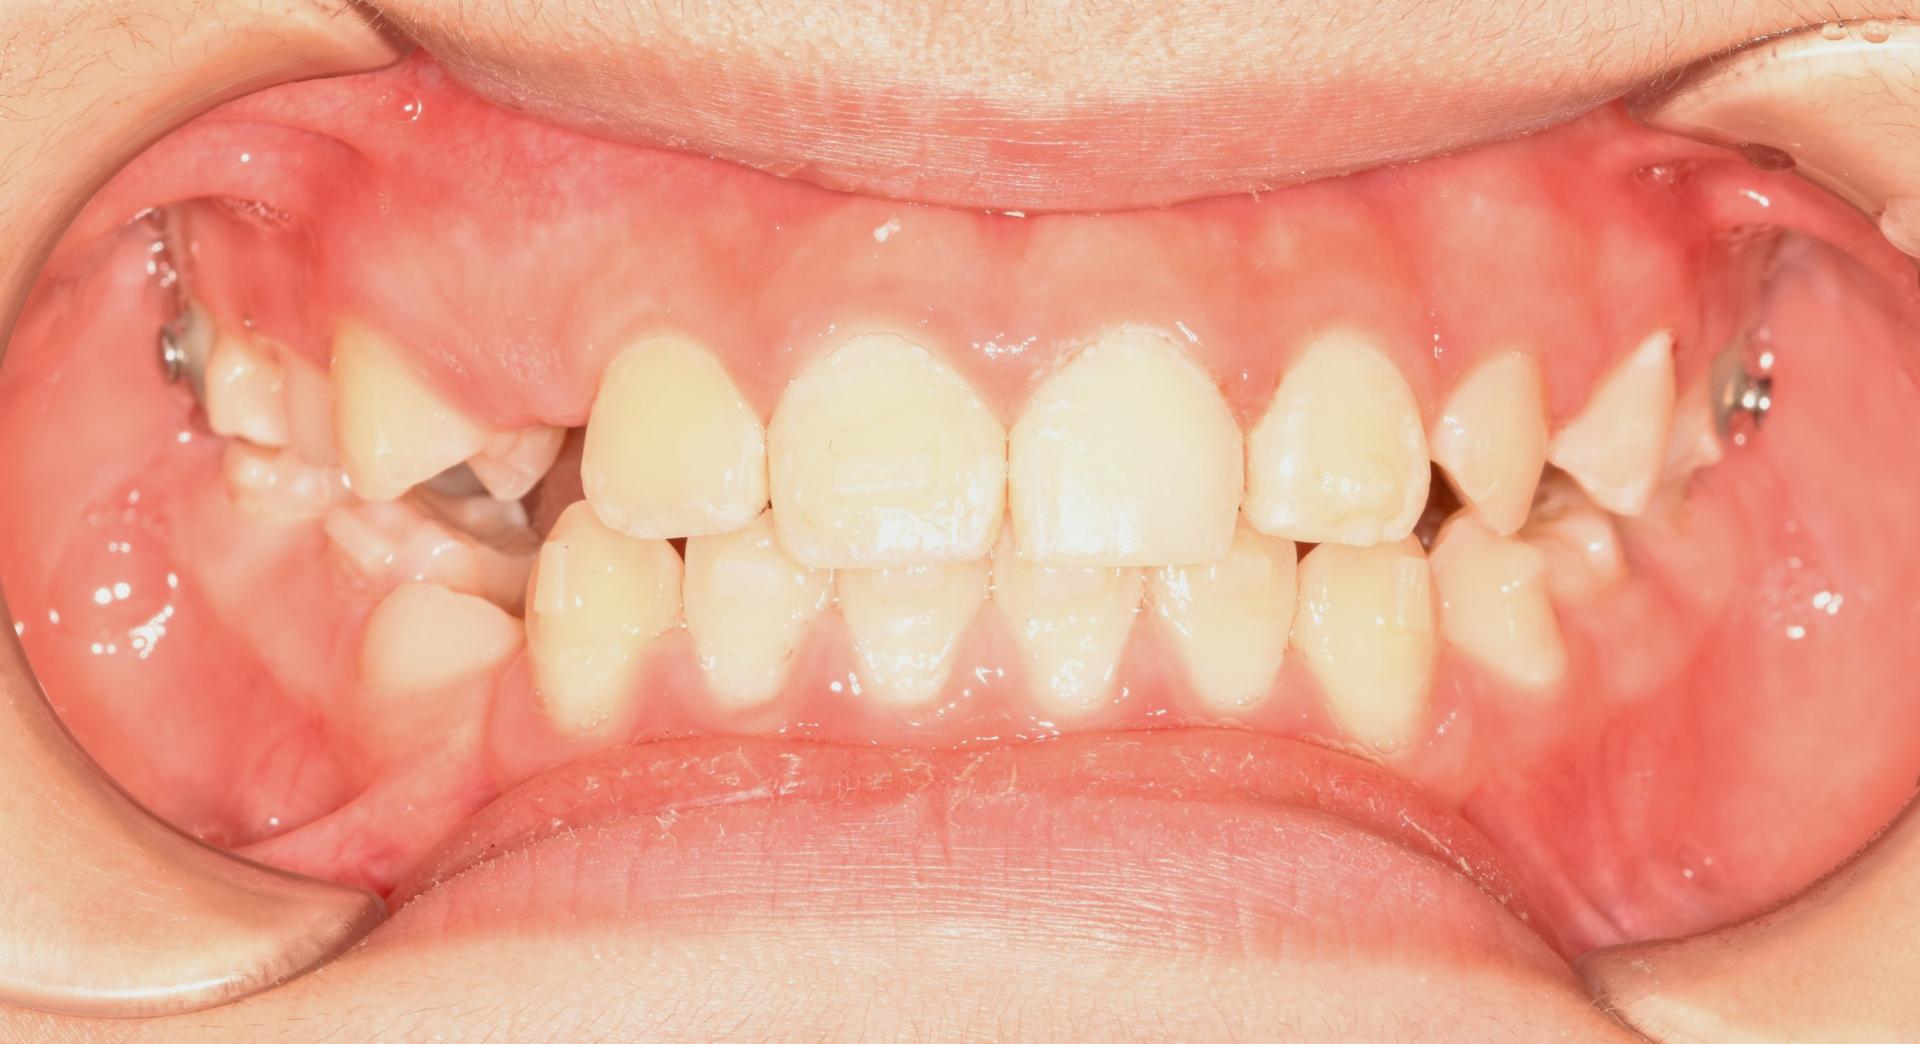

1년반의 투명교정이 끝나고 치아가 예쁘게 자리 잡았습니다.

아래쪽 새로 나오는 어금니가 뒤로 기울어져나네요. 맹출을 더 기다린뒤 자연적인 해소가 안되면 부분적으로 해결해주기로 하였습니다. 제가 교정을 해준 친구.. 끝까지 예쁘게 해줄거에요♥

얼굴도 많이 예뻐졌어요!

1년 반의 기간 동안 장치를 성실하게 껴준 멋진 아이입니다.^^